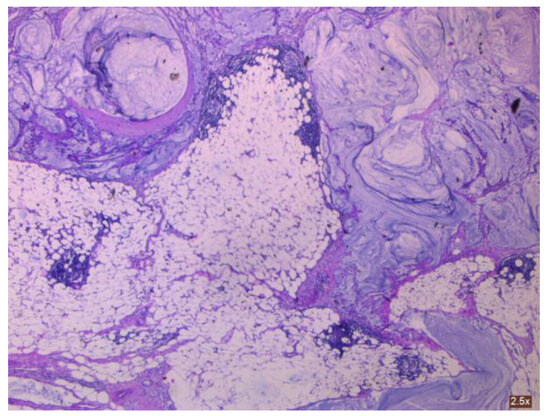

3.1.1. Mucinous Cystadenoma